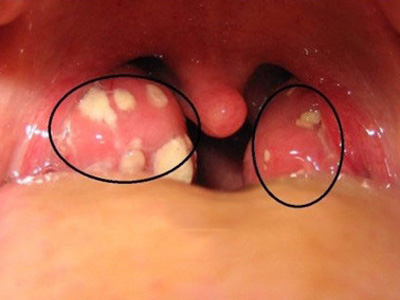

扁桃体结石是指发生在扁桃体隐窝的结石,是扁桃体隐窝细胞聚集所致的灰白色钙化团,扁桃体结石临床较少见。

扁桃体结石多呈灰白色,表面粗糙,质地坚硬。部分患者可自觉咽部有异物,结石较大者,进食可出现阻挡感。并发扁桃体炎症时,可出现患侧扁桃体肿大、咽痒、刺激性咳嗽等症状,甚则可出现咽喉肿痛、吞咽困难、发热等全身症状。

扁桃体内可发现灰白色、质地较硬的细小沙石,或可在肿大的扁桃体内触及较硬的肿块,触时有微痛感。